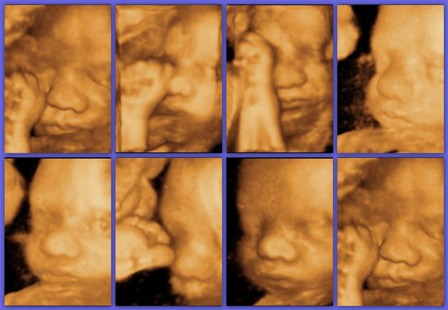

Kép

A kisfiam :wink:

Szia Krisztina üdvözlünk közöttünk!!!Cuki a fiad, olyan kis pufók.

Pici fiú (nem is annyira pici--UH szerint olyan 3 kg körüli már most :roll: ) a David nevet fogja kapni.

UH-képeken időnként úgy néz ki, mint aki éppen duzzogott :wink:

Ausztriában lakunk, itt fogok szülni a tartományi kórházban...

Kriszti:üdv itt!Nagyon formás Dávid baba!

Kriszta, üdvözöllek én is a csapatban! Édes a kis David! Továbbra is probléma mentes babavárást kívánok! :wink:

szia, üdv itt. Én is Kriszti, és 86-os évjárat! :D :D Gyönyörű kisfiad van, nagyon takaros, formás babuci! :D

Kriszta! Üdv köztünk!!! :D Nagyon szép babád van! :lol:

Kriszta, üdv itt, és csodaszép a pici fiad a képeken!!!